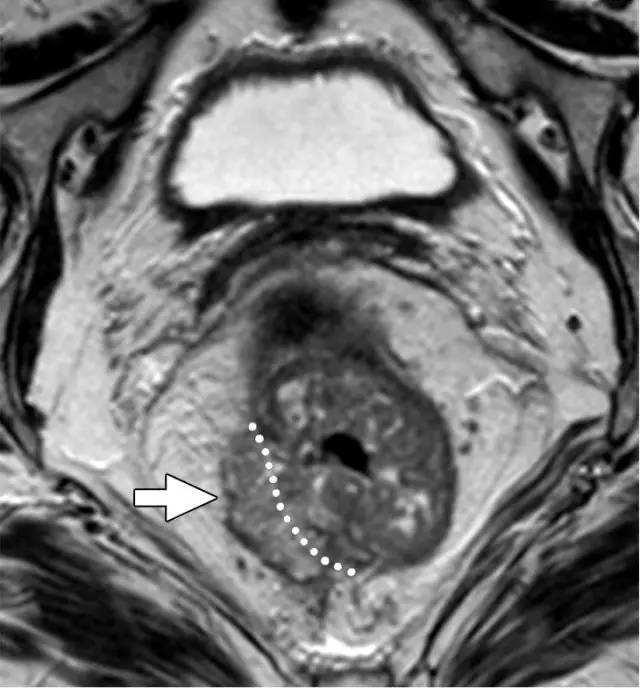

环周切缘 CRM

直肠系膜筋膜是包围直肠周围脂肪和直肠的低信号,代表 TME 切除术中的手术切除平面。在 MR 图像上,是进行 TME 手术患者的潜在 CRM。CRM 阳性是局部复发和预后差的一个重要的独立预后因素。

图 31 轴向 T2 加权图像报告 CRM 的距离。T3d 肿瘤局限于固有肌层内,肿瘤毗邻直肠系膜筋膜(箭头;肿瘤为 T2)。侵犯边界似乎是左后方(白色箭头),肿瘤的 CRM 评估为 5 mm。但有两个混合信号强度淋巴结(黑色箭头)邻接直肠,导致 CRM 为 0 mm。